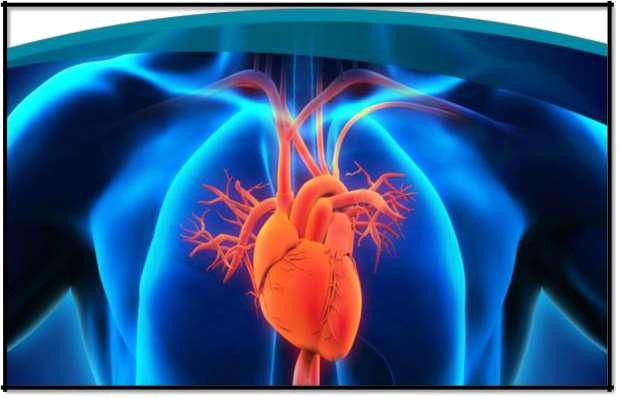

Valvular Heart Disease

This condition is where the valves in your heart that control the free flow of blood are not working properly. The valves of the heart ensure that your blood freely flows in a forward direction and cannot leak backward. The way in which a healthy heart operates is the same for everyone.

The heart contains four chambers with the heart valves placed at the exit of each chamber. The blood flows through both your right and left atria into the ventricles through the mitral and tricuspid valves. When your ventricle chambers are full, the valves will shut, stopping the blood from returning to the atria when the ventricles contract. When the ventricles start to contract, the aortic and pulmonic valves are forced to open. The blood from the left ventricle goes into the aorta and then to the rest of the body after passing through the aortic valve. The blood from the right ventricle goes into the pulmonary artery through the pulmonic valve.

Once the ventricles are done contracting and begin to relax, both the valves are shut. This prevents any blood from flowing back. This process repeats itself throughout an entire lifetime. There are two main types of heart valve disease.

Valvular stenosis occurs when one or more valves are narrowed, stiffened, thickened or blocked. It can lead to the heart pump insufficiency, and there'll be a lack of blood on different body parts. All four of the heart valves can develop stenosis.

The other common type is valvular insufficiency. This happens when a heart valve does not seal or close properly, allowing some blood to be forced or leak back into the chamber. If this condition worsens, it forces the heart to work harder to supply the needed blood to the body.